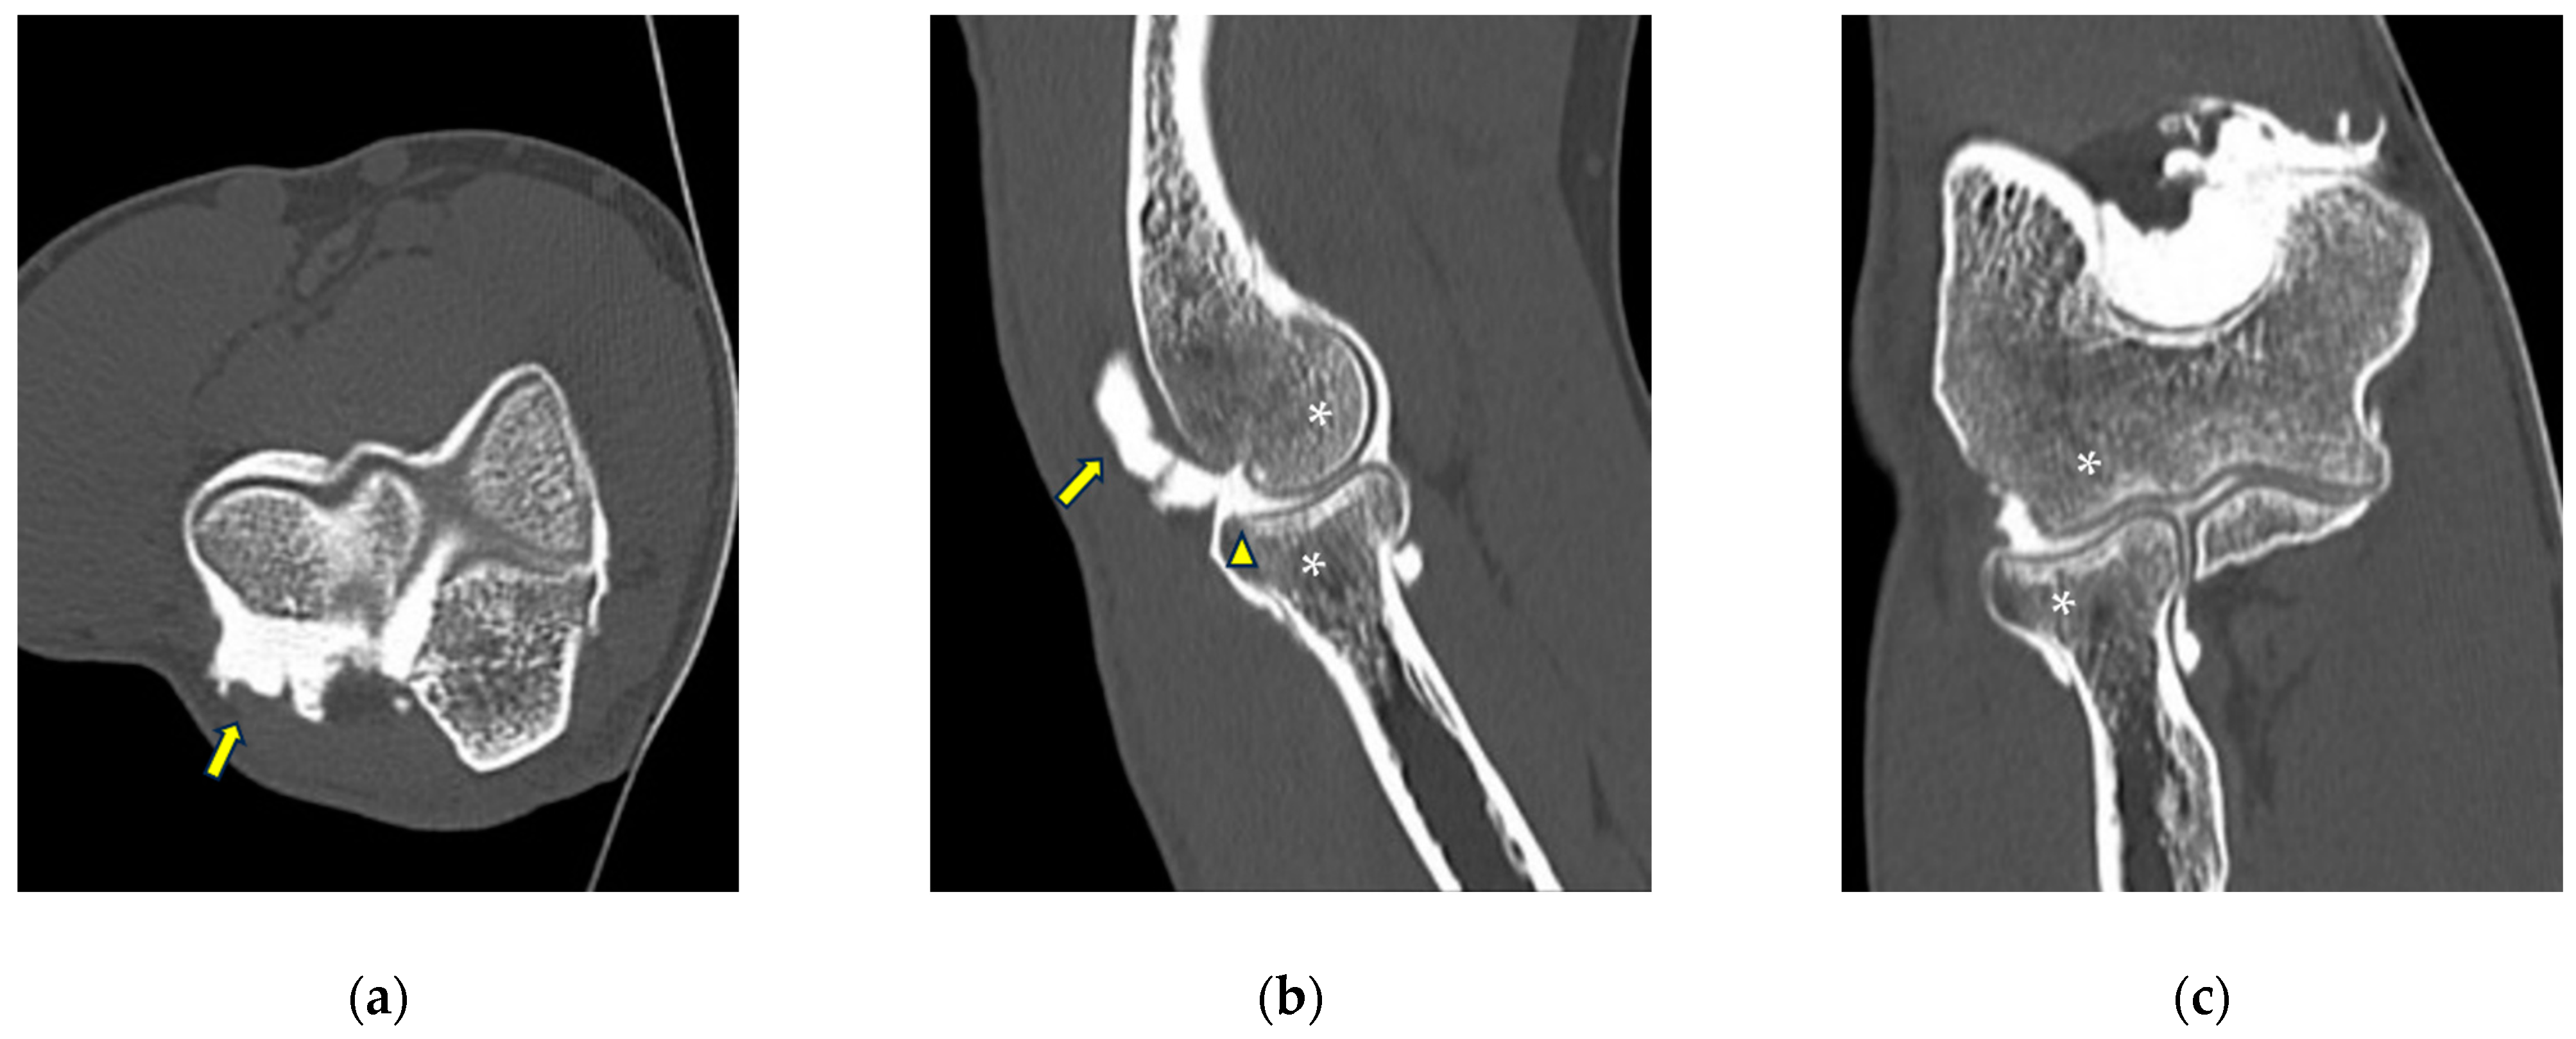

Figure 3.

CT arthrography of a patient with chronic elbow instability. (a) Sagittal image shows pitting and fissuring of radial head cartilage, involving >50% of its thickness (grade III) (white arrows); (b) coronal reformat of the same patient shows a focal full-thickness cartilage defect of the anteromedial radial head (grade IV) (white arrow). In the same image, mature calcifications can be seen at the insertion of the common extensor tendon (white arrowhead).

Figure 4.

CT-arthrography of a patient with rheumatoid arthritis. (a) Sagittal image shows pathological widening of the anterior humero-ulnar recess (asterisk), osteophytosis of the coronoid process (white arrowhead) and a distended posterior recess containing multiple non-calcific loose bodies compatible with secondary synovial chondromatosis (yellow arrowheads); (b) coronal image shows abnormal morphology and complete chondral erosion of both the radial head dish and lateral humeral condyle (yellow arrows).